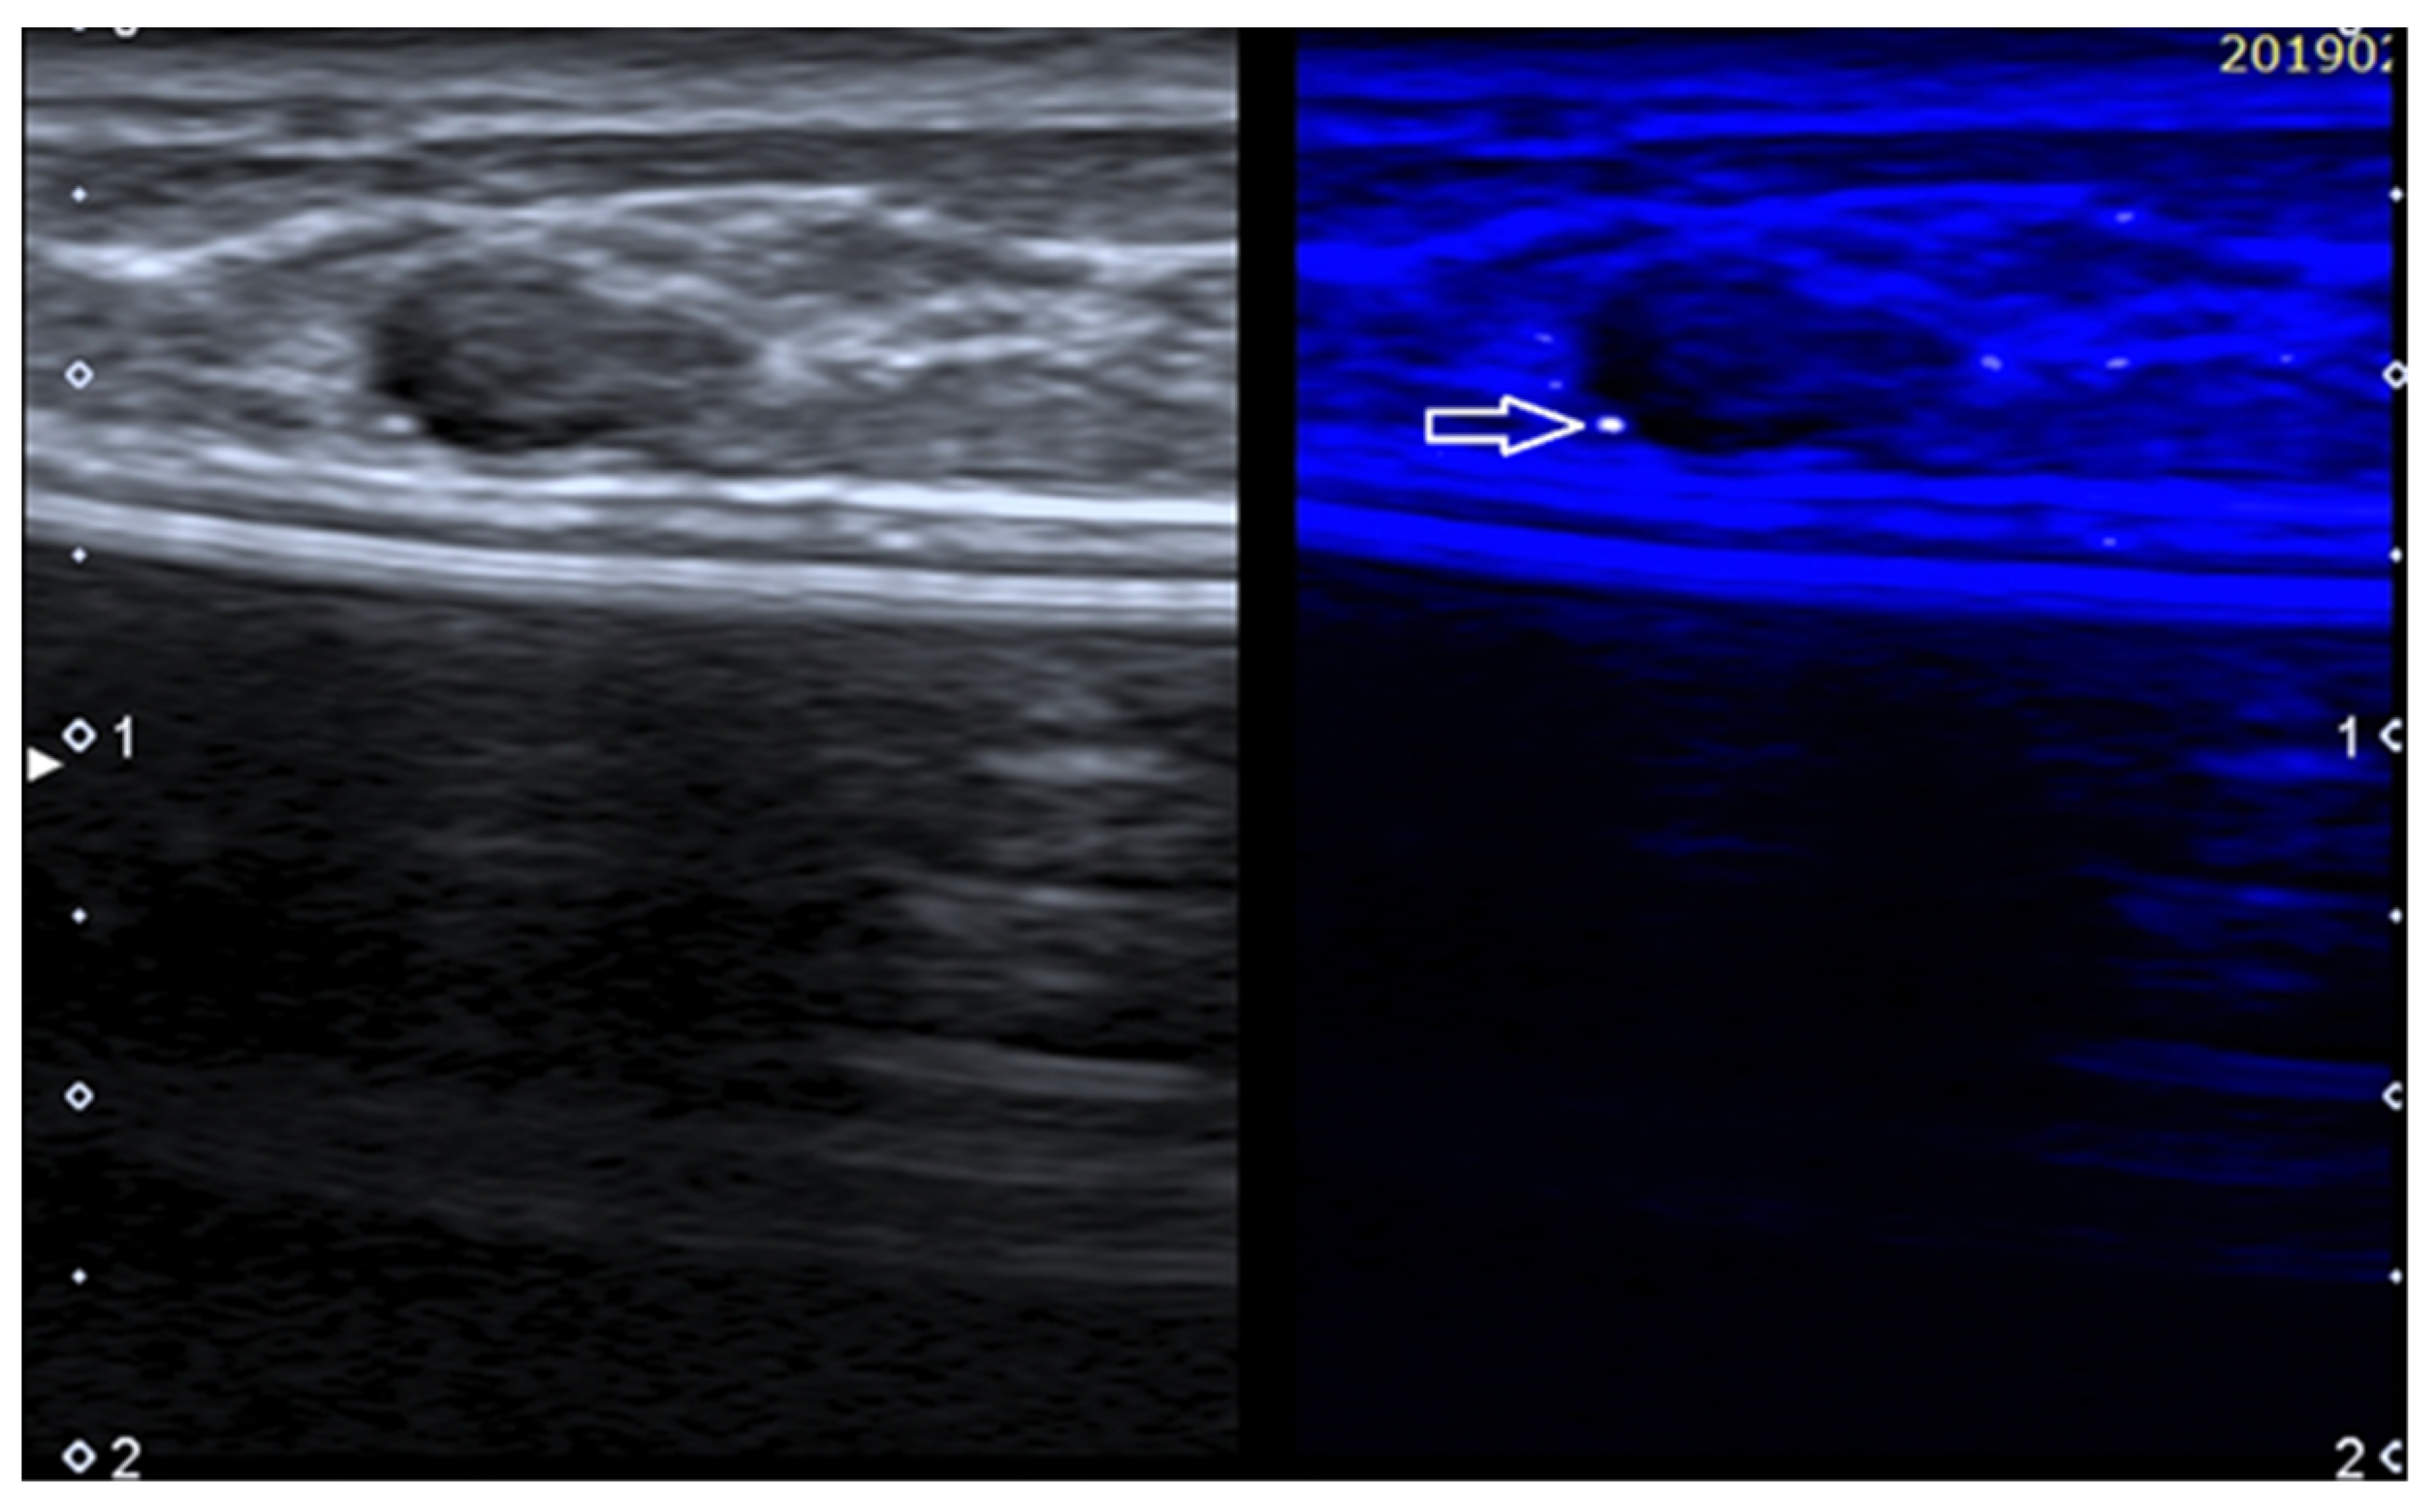

Figure 6. Fibroadenoma in a patient with history of augmentation mammoplasty. MicroPure allows to easily detect a bright dot (arrow) due to a small calcification.

Grouped microcalcifications represent a very important finding in breast imaging and a significant US limitation, being hard or impossible to detect, particularly if not associated with a nodule [75]. MicroPureTM is a software from Canon (Tokyo, Japan) that allows to highlight microcalcifications (Figure 6).

MicroPure combines non-linear imaging with speckle suppression, extracting the calcification from the heterogeneous background. Filtered microcalcifications are shown as bright dots inside a dark blue background overimposed to a grayscale US.